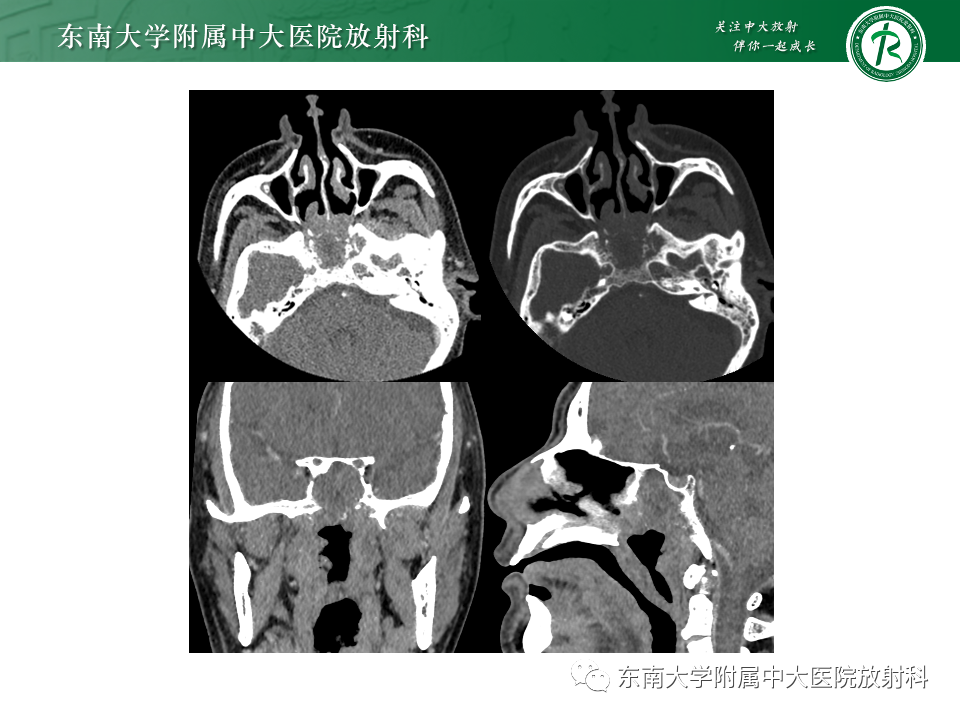

病例1:脊索瘤

病例2:弥漫大B细胞淋巴瘤

病例3:侵袭性垂体瘤

病例4:鼻咽癌